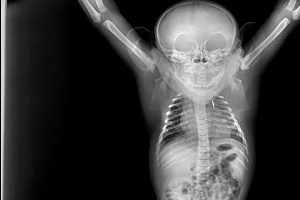

Este procedimiento diagnóstico permite a nuestros expertos brindar una excelente atención médica. Al exponerlos a los rayos X, el equipo puede tomar fotografías de las partes óseas internas de los animales, comprobando la existencia de lesiones o enfermedades que a simple vista no podrían ser identificadas.

En el caso de los animales considerados peligrosos para su manejo requieren de un proceso de anestesia previo a la toma de radiografías, pero siempre asegurando su estado de salud. Sin embargo, otros no necesitan de esta inmovilización química para hacerles radiografías.

Por supuesto, para la realización de todo procedimiento diagnóstico o manejo veterinario, el equipo de Bioparc Fuengirola se asegura de que los animales no sufran ningún tipo de estrés adicional al examen médico, rutinario o de urgencia.

¿Sabrías identificar de qué animal se trata?

- Chimpancé